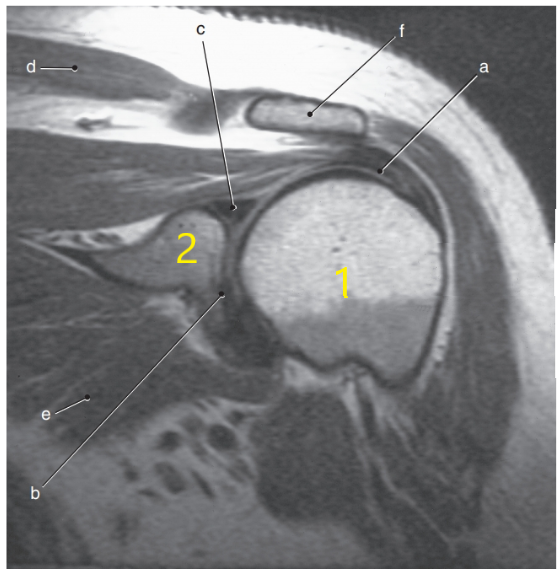

What anatomy is # 2 ?

Scapula

What anatomy is # 1 ?

Humeral head

What is letter c ?

Superior glenoid labrum

What is letter f ?

Acromion process

What is letter a?

Median nerve

What is letter e ?

Olecranon process

Glenohumeral joint

What is letter d ?

Acromioclavicular ligament